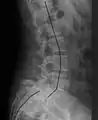

| X-ray of the lateral lumbar spine with a grade III anterolisthesis at the L5-S1 level. | |

- Grade III: 50–75%